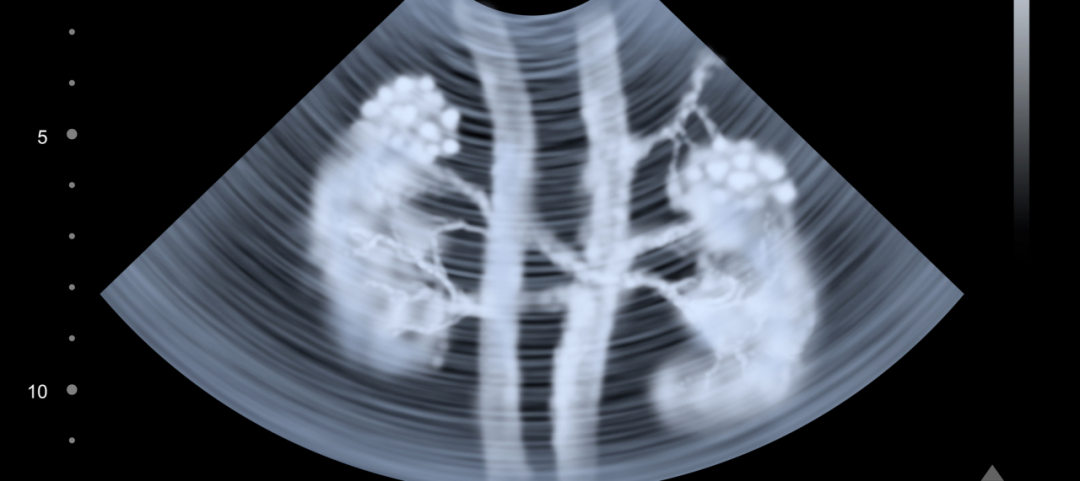

Ogni malattia renale può avere conseguenze sulla gravidanza. Questo non significa necessariamente che ne sia un limite o che possa incidere sulla possibile perdita del piccolo o che possa causare malformazioni fetali intrauterine, però è importante ricordare l'estrema necessità di controlli continui. Ad evidenziare queste conclusioni è lo studio condotto dai ricercatori dell'università di Torino e quelli dell’ospedale Brotzu di Cagliari, pubblicato sul Journal of American Society of Nephrology. Gli studiosi italiani, infatti, dopo aver monitorato 504 donne incinte con una patologia renale cronica ed 836 senza problemi di funzionalità renale, hanno appurato che qualunque livello di malattia renale può determinare problemi in gravidanza, dalla cicatrice per un episodio di calcoli alla malattia cronica.

Una patologia renale, a prescindere dalla sua entità, può avere conseguenze sulla gestazione e può causare un parto prematuro, il ricovero in terapia intensiva neonatale per il piccolo o ipertensione nella madre. Non è il caso di allarmarsi o di ritenere preclusa ogni possibilità di maternità in caso di malattia renale lieve, media o grave che sia, perché, come precisa la coordinatrice dello studio italiano, dottoressa Giorgina Barbara Piccoli, quello che serve anche in questi casi è «un attento follow-up a cui vanno però sottoposte tutte le mamme in dolce attesa». Se in passato proseguire una gravidanza in presenza di una patologia renale era sconsigliato, oggi si ritiene che possa essere portata a termine con esito positivo, con le dovute attenzioni. Vietato scoraggiarsi, quindi, la cicogna non discrimina!